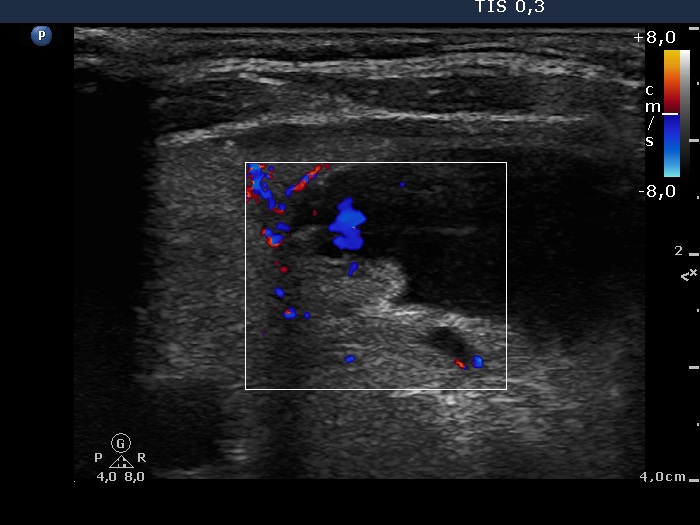

Right lobe, longitudinal scan, color Doppler mode. Perinodular blood flow is demonstrated.